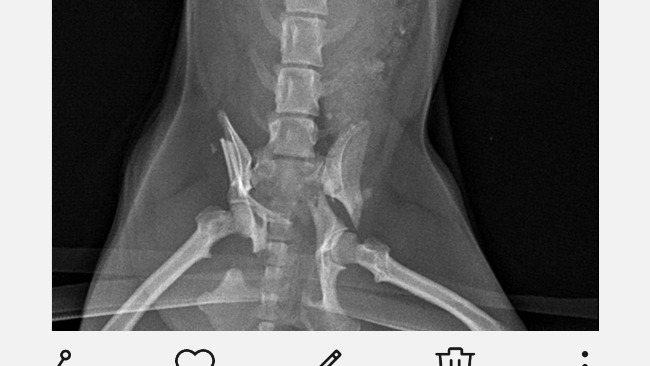

Witam. Jestem malutka Sisi. Do tej pory byłam bardzo energicznym psiakiem. Wszędzie mnie było pełno... Ciągle coś psocilam i byłam zawsze na pierwszym miejscu. Niestety zdarzył się wypadek. Kiedy wieczorem biegałam sobie wraz z moimi siostrami nadjeżdżał motor. Z ciekawości kto to pobiegłyśmy się przywitać... Moje siostry się tylko przyglądały a ja niestyty podbiegłam za blisko. Nie było już ucieczki.. Wpadła wprost pod koła motocyklisty....zatrzymal się i zobaczył ze leżę nieruchomo. Moj tatuś szybko wziął mnie na ręce i zawiózł do szpitala. Pozostałam tam przez 2 dni... Diagnoza straszna... Potrzaskana miednica... Okropnie mnie boli... Potrzebna jest pilna operacja ponieważ nie będę mogła już chodzić i odłamki kości mogą naruszyć narządy wewnętrzne...co może doprowadzić do mojej smierci. Moi rodzice chcą mi pomóc za wszelką cenę... Czuwają przy mnie dniami i nocami gdy ja płaczę tulą mnie do siebie. Jednak to nie wystarczy potrzebne są pieniądze żeby opłacić operacje. Po niesione koszty już to ok 600zl.sama operacja kosztuje ponad 3 tysiące a do tego jeszcze rehabilitacja. Bardzo proszę o choćby najmniejsza wpłatę. Odciąży to moich najbliższych w przeciwnym razie będę skazana na śmierć lub w najlepszym wypadku.na kalectwo .